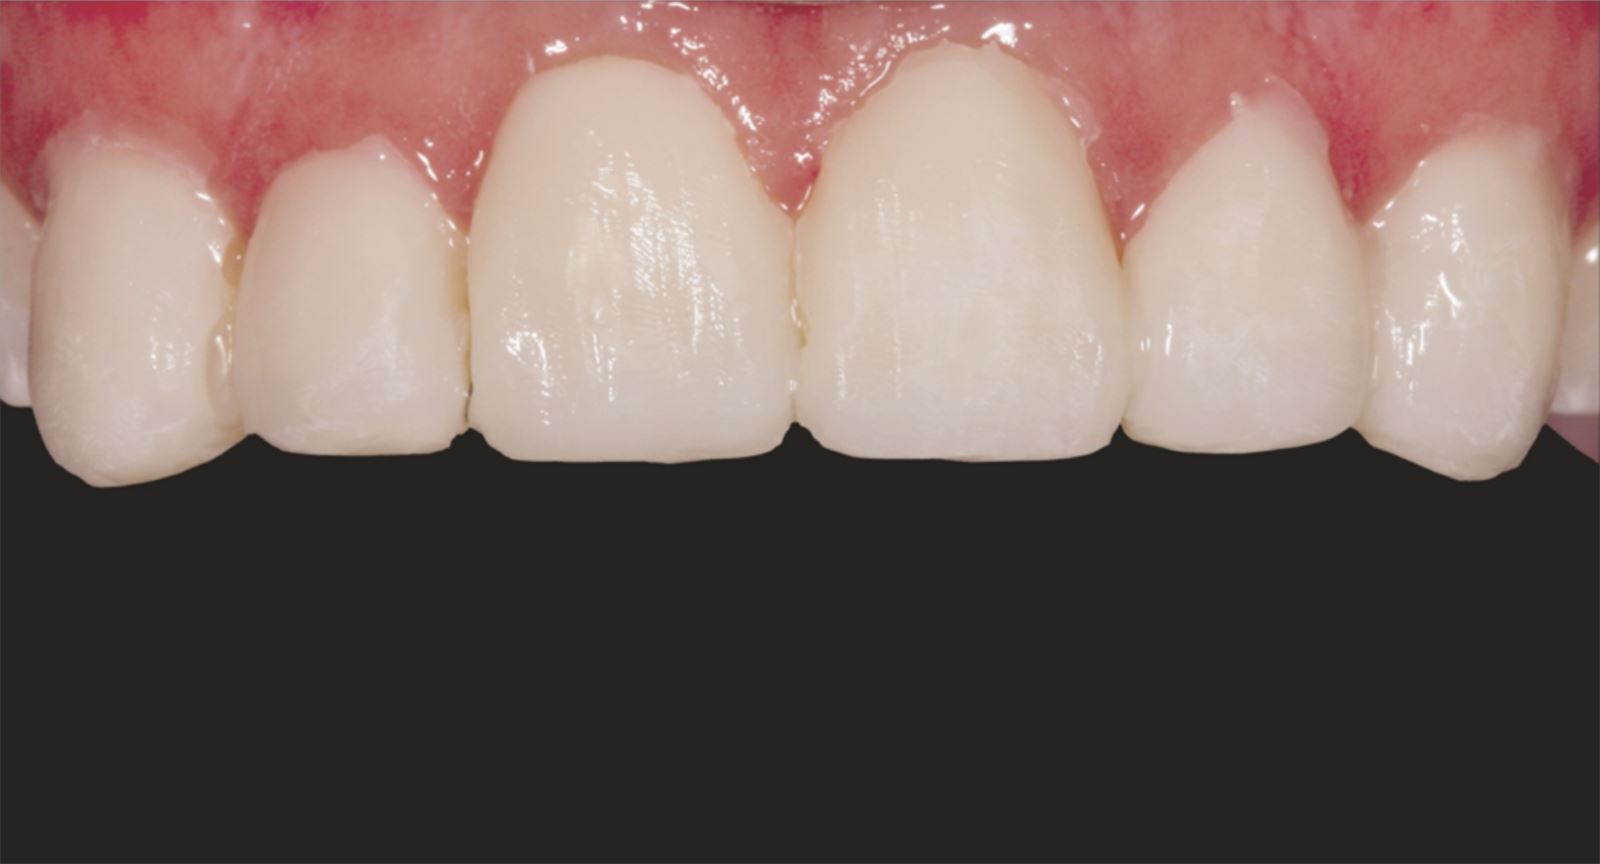

Mladá žena vo veku okolo 20 rokov, ktorú trápila diskolorácia horných frontálnych zubov po skoršej traume, vyhľadala ošetrenie u Dr. Jaleeny Fischer-Jessop, DDS, MBA. Hľadala riešenie, ktoré by obnovilo jej úsmev. Pacientka bola ošetrená konzervatívnou a cenovo dostupnou metódou: kompozitnými fazetami bez preparácie, priamym bondingom. Dr. Fischer-Jessop zvolila tento postup na prekrytie diskolorácie a zjednotenia horných zubov s dolnými frontálnymi – bez nutnosti invazívnejších výkonov, ako sú implantáty, alebo nákladných laboratórne zhotovovaných faziet. Na zosvetlenie zubov boli vybrané odtiene B1D a Enamel White (EW) a odtieň Universal Body (UB) kompozitu Transcend™ bol použitý na prirodzené splynutie okraja v cervikálnych oblastiach.

Kompozit Transcend v odtieni B1D bol aplikovaný od dvoch tretín výšky korunky od incisálnej hrany smerom k cervikálnej oblasti, kde sa postupne stenčoval. Odtieň Universal Body (UB) bol nanesený v cervikálnom tretine, záverečné vrstvy tvoril Enamel White (EW) a malé množstvo UB v marginálnej oblasti pre prirodzené splynutie.

Tento postup úspešne vyriešil estetické obavy pacientky prekrytím diskolorácie horných frontálnych zubov a dosiahnutím prirodzeného, vyváženého vzhľadu vo vzťahu k dolným frontom. Použitie kompozitných faziet bez preparácie poskytlo konzervatívne, vysoko efektívne riešenie, ktoré rešpektovalo finančné možnosti pacientky a jej požiadavku na minimálne invazívny prístup.